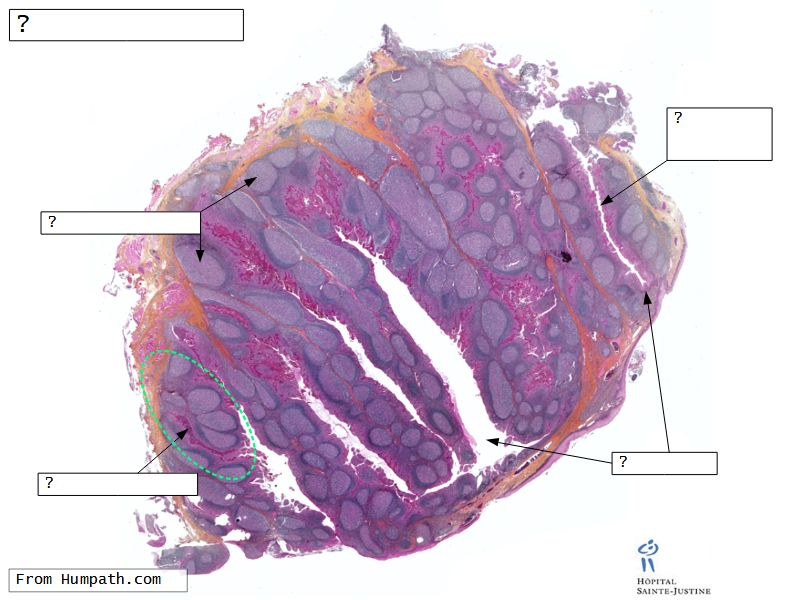

Fill in all the missing labels, and assess as you move through the slides. Answers on the down slide. It is important to do this using pen and paper, and not just glance through the images.